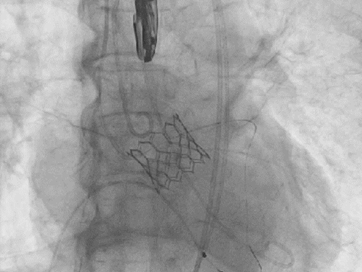

术中关键步骤影像:

25mm球囊预扩

29mm S3瓣膜-3cc释放

瓣膜释放影像